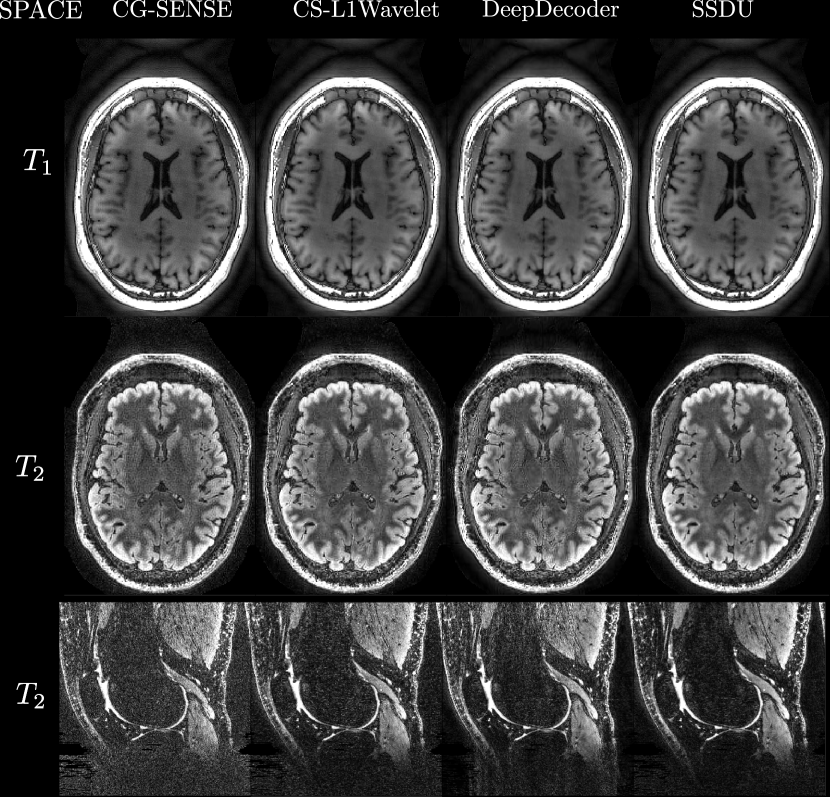

Figures 4, 5 show axial MPRAGE brain slices at the different field strengths and corresponding closeups of the cerebellum and the left frontal lobe. Figure 6 shows a sagittal PD knee slice (3T) with closeups of articular cartilage interfaces in sagittal (femur) and axial (patella) views. These show the generalizability of the methods to different magnetic field strengths as well as changes in anatomy and contrast. Example reconstructions for the other sequences can be found in the Appendix 8, 9.

Qualitatively, we can see from Figures 4, 5, 6 that all methods are able to generalize well (in the sense of approximately preserving performance/appearance on dataset used for training/tuning) to changing field strengths, anatomy, and contrast, although changing anatomy clearly worsened absolute image quality as compared to changing field strength. DeepDecoder preserves its spatially varying smoothing/artifacts, and SSDU/CS-L1Wavelet are able to produce images with less noise and comparable sharpness to CG-SENSE, although CS-L1Wavelet exhibits more artifacts. As expected, the perceptual quality of all methods increase with increasing field strength due to higher spatial resolution. Differences between the methods are less pronounced in the knee scan although overall image quality is worse.